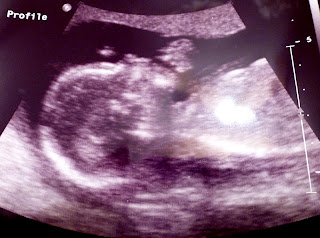

Here's our little Pula and his profile.

As soon as the ultrasound technician went over an area of our little baby I recognized exactly what that tiny arrow was pointing to.

I suppose that we are awfully good at making little boys.

Although these two pictures (above and below) might seem insignificant in many ways... seeing Pula's opened hand was a blessing (since clenched hands would have been an indicator in signs for Trisomy 18.)

Another wave from Pula. So happy to see five little fingers pass over the screen.

Again... (I know these pictures are a little difficult to see, taking a picture of a picture isn't easy, but you get the idea--hopefully--) here are Pula's ten tiny toes and we couldn't have been happier to see his perfect little feet. (No rocker bottom feet on our baby boy.)